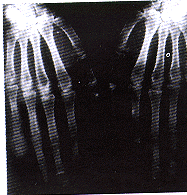

X线检查(包括颌骨、两手、右上肢、两侧锁骨及骨盆):上下齿槽骨骨质明显吸收;两手末节指骨除左无名指外,均呈膨胀性溶骨性破坏(图2);右尺骨近端背侧、左锁骨中段、右髋关节内下缘泪点旁及右股骨颈处均可见囊性破坏区。组织病理检查(头皮及左耳廓皮损):表皮基本正常。真皮中、深层有由细胞和基质构成的肿瘤,瘤体内血管较丰富(图3),细胞核圆形或椭圆形,有的为双核,胞浆丰富、淡染,有的呈空泡状,有的呈网状,有的胞浆中有嗜酸性细小颗粒,周围的间质呈均质嗜伊红性(图4)。两块标本病变一致。PAS染色阳性。

图2 幼年性透明蛋白纤维瘤病手部X线

表现,末节指骨膨胀性溶骨性破坏